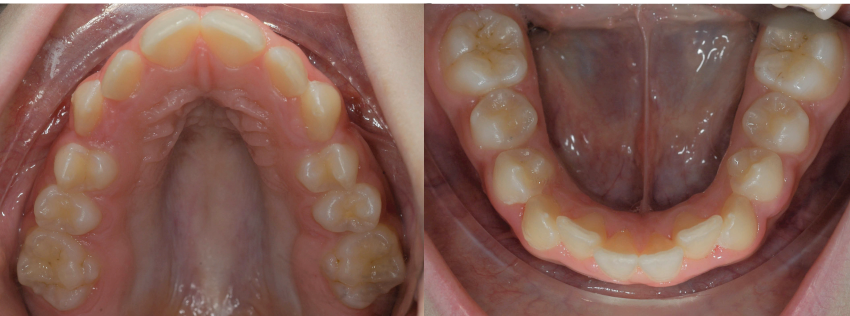

_Materiale e metodi Una paziente di sesso femminile di 11 anni, presenta all’esame clinico: dentizione permanente, palato di forma ogivale, discrepanza trasversale, affollamento e contrazione dell’arcata superiore, tipping vestibolare dei primi molari superiori, marcato affollamento dentale inferiore, tipping linguale degli elementi dentali postero-inferiori, proinclinazione vestibolare degli incisivi inferiori (Fig. 1). La paziente, inoltre, riferisce il menarca sei mesi prima dell’inizio della terapia. Per prima cosa è stato realizzato un setup digitale del risultato finale nell’arcata inferiore correggendo l’affollamento mediante espansione dei settori posteriori e minimizzando la proinclinazione degli incisivi. Utilizzando questo setup digitale come arcata guida, è risultata una discrepanza trasversale tra arcata inferiore e arcata superiore di circa 6 mm (Fig. 2).Richiesto l’esame CBCT, è stata valutata anche la morfologia della sutura palatina ed è risultata di tipo C secondo la classificazione di Angelieri et al11 (Fig. 3).

Fig. 1_Situazione intraorale a inizio terapia.

Fig. 2_Setup finale della correzione dell’arcata inferiore: nell’immagine è rappresentato in blu la posizione iniziale della dentatura, in bianco la posizione risultante dal setup. La lunghezza trasversale prevista a fine terapia sarà di 50 mm.